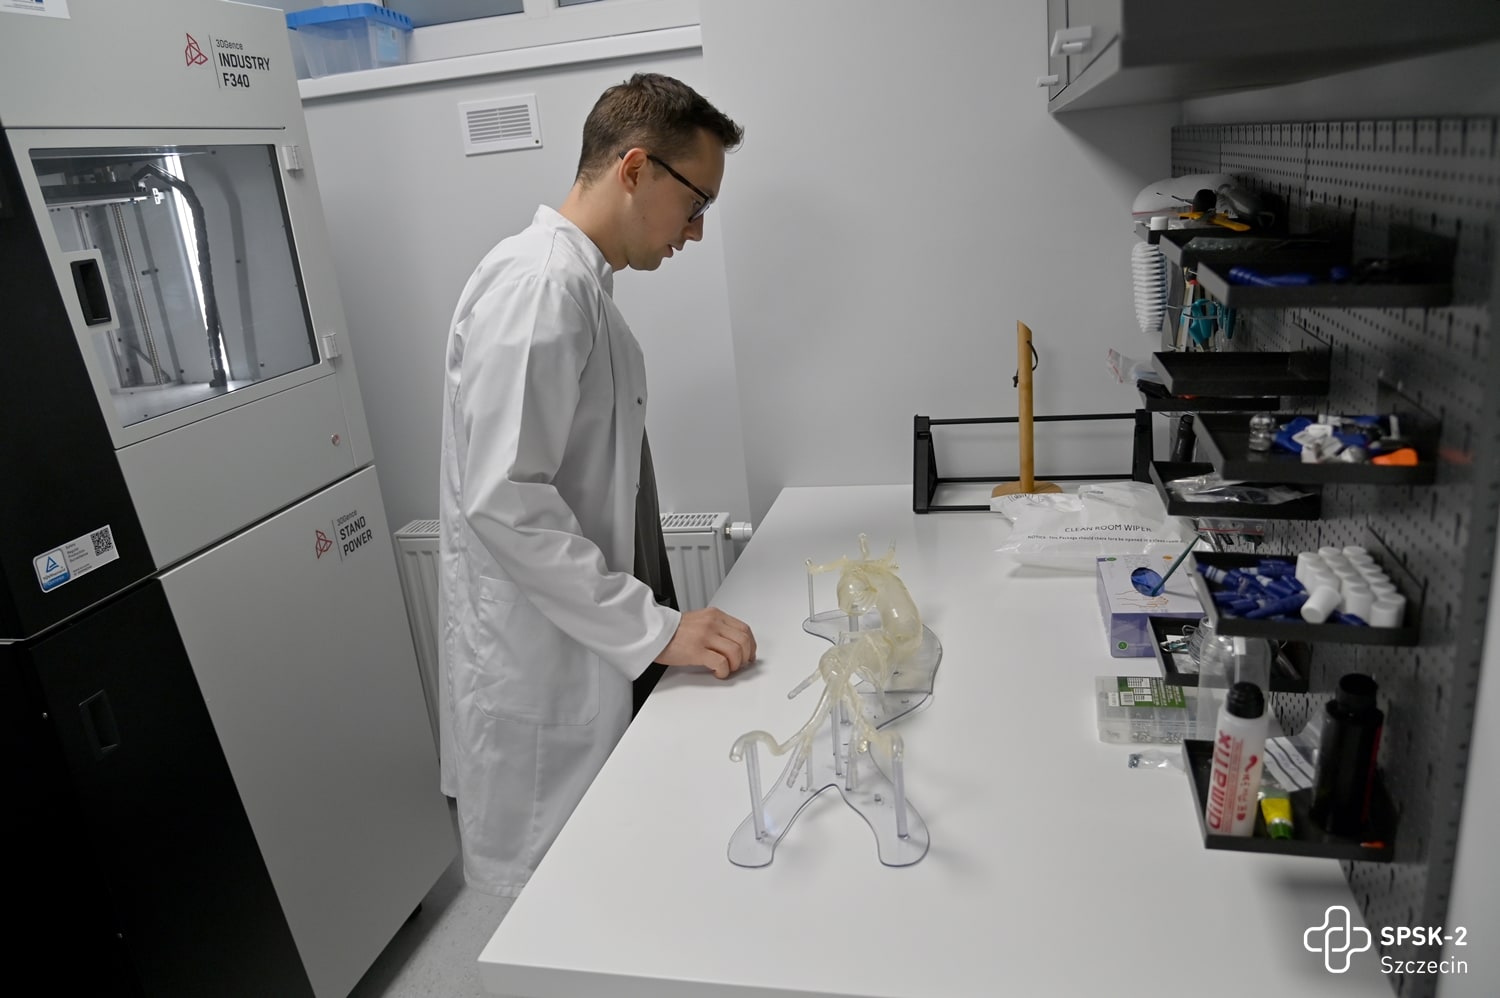

Oprócz badań USG chętni mogli zaznajomić się z najnowszymi metodami leczenia tętniaków aorty, obejrzeć filmy, w których nasi chirurdzy naczyniowi opowiadają o zagrożeniach chorobami naczyniowymi, zobaczyć na własne oczy czym jest tętniak i jak wygląda, obejrzeć wydrukowane w Ośrodku Technologii Medycznych 3D naszego szpitala modele organów człowieka, oraz poczuć się jak chirurg podczas operacji i dzięki goglom Hololens i wyświetlanemu w nich obrazowi rozszerzonej rzeczywistości ponawigować obrazem tomografii komputerowej i dokładnie obejrzeć struktury anatomiczne człowieka.

Pielęgniarki i położne naszego szpitala: Aleksandra Dreas, Alicja Kapała, Klaudia Kokoszka, Ewa Kubiak oraz stażyści i studenci Pomorskiego Uniwersytetu Medycznego w Szczecinie: Katarzyna Czarnecka, Karolina Kalembkiewicz, Michał Kargul, Dominika Kucharska, Karolina Seidler, Urszula Sielicka, Patryk Skórka, Claudia Wietrzykowska mierzyli ciśnienie, poziom glukozy we krwi i przeprowadzali wstępną kwalifikację pacjentów do badań oraz pokazywali jak rozszerzona rzeczywistość pomaga zobaczyć to, czego nie widać gołym okiem. Dr n. med. Paweł Rynio, chirurg naczyniowy i kierownik projektu – chętnie opowiadał o chorobach naczyniowych i tłumaczył m.in. jak technologia druku 3D wspiera medycynę.

Wydarzenie zrealizowane zostało w ramach projektu: „Rozwój i wzmacnianie transgranicznej współpracy w zakresie innowacyjnego zastosowania wirtualnych i drukowanych modeli 3D chorób w spersonalizowanej medycynie zabiegowej XXI wieku”, w ramach Programu Współpracy Interreg VA Meklemburgia-Pomorze Przednie / Brandenburgia / Polska w ramach celu „Europejska Współpraca Terytorialna” Europejskiego Funduszu Rozwoju Regionalnego (EFRR). Partnerem projektu jest Medyczny Uniwersytet w Greifswaldzie.

Jedyny w kraju Ośrodek Medycznych Technologii 3D otwarty!

2022-10-13Po kilku latach wyczekiwania 7 października 2022 roku odbyła się uroczystość formalnego rozpoczęcia działalności nowoczesnego Ośrodka Medycznych Technologii 3D. To jedyna taka w Polsce, pierwsza, niepowtarzalna jednostka, która łączy zaawansowane technologie druku 3D, gogle mieszanej rzeczywistości i medycynę! Korzystać z tego będą mogły wszystkie dziedziny medycyny, nie tylko szczecińskich, czy polskich szpitali.

Celem Ośrodka Medycznych Technologii 3D jest:

- optymalizowanie sposobów leczenia

- indywidualizowanie opieki nad pacjentem, poprzez tworzenie trójwymiarowych modeli organów pacjenta

- rozwijanie i polepszanie metod operacyjnych.

Dostępne na co dzień dwuwymiarowe wyniki badań chorego – tomografia komputerowa, czy rezonans magnetyczny, to lata temu był skok w przyszłość. Dziś to już trochę za mało. Trzeci wymiar obrazu struktur anatomicznych chorego to ten element, który niezwykle ułatwia pracę lekarzowi. By stworzyć trójwymiarowy obraz z pomocą przychodzi druk 3D oraz hologramy.

W Ośrodku Medycznych Technologii 3D (OMT3D) powstać będą trójwymiarowe modele organów pacjentów – prawidłowe lub ze zmianami patologicznymi. Wydruk będzie powstawał w najnowszej generacji drukarkach 3D, umożliwiających druk nie tylko dowolnych struktur anatomicznych pacjenta z ich patologiami, ale odwzorowujących także kolory, strukturę, giętkość i twardość prawdziwych organów i tkanek. A dzięki goglom Hololens2, operujący lekarz będzie w powietrzu nawigował hologramem, przedstawiającym zdjęcia diagnostyki obrazowej pacjenta.

Pomysłodawcą powstania ośrodka jest dr n. med. Paweł Rynio – młody lekarz, chirurg naczyniowy, który rozwinął ideę w ramach programu Interreg VA, w którym partnerem naszego szpitala jest Uniwersytet Medyczny w Greifswaldzie. Jak mówił podczas uroczystości otwarcia Ośrodka przedstawiciel partnera - prof. Maciej Patrzyk – „Trzeci wymiar obrazu diagnostycznego pacjenta to było coś, czego brakowało lekarzom w medycynie. Płaskie obrazy nie oddają rzeczywistości na tyle dokładnie. Kiedy zobaczyłem w telewizji, że zespół prof. Gutowskiego w szpitalu w Szczecinie wykorzystuje druk 3D i gogle mieszanej rzeczywistości, wiedziałem, że tego szukam. Kiedy więc dr Rynio zadzwonił do mnie, to razu przystałem na współpracę”